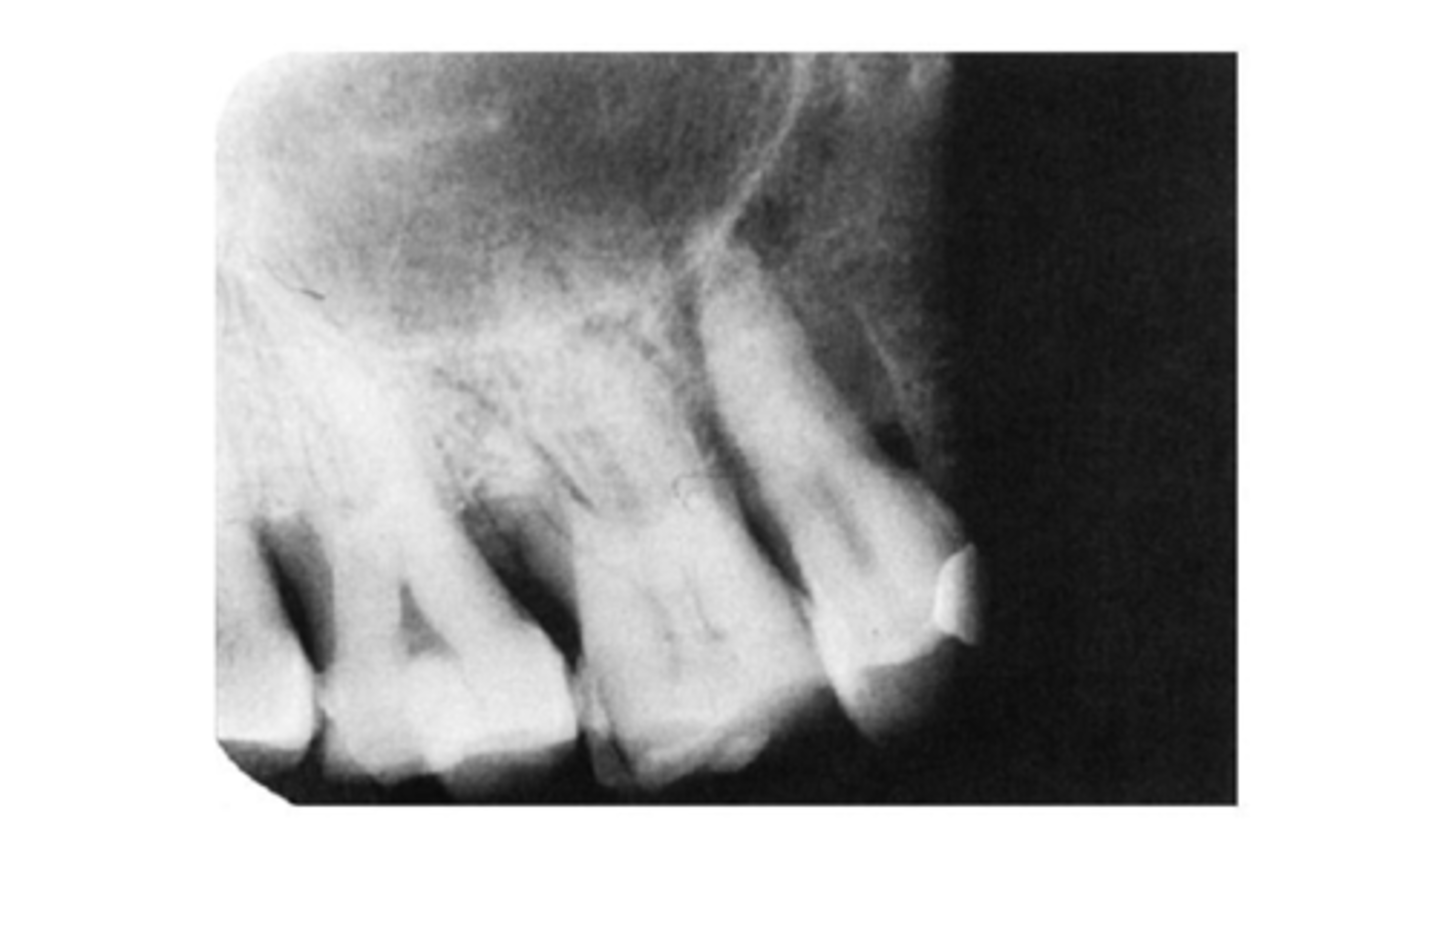

Incorrect Vertical Angulation-->Elongated Images

-Teeth appear long and distorted

-Vertical angulation was insufficient or too flat, resulting in images that are longer then the actual teeth.

-Occurs more often with the bisecting technique

-To prevent use adequate vertical angulation

Tube Head & PID-->Elongation of the Image

-Bisecting technique error

-Insufficient Angulation (not steep enough), causing elongation or increased anatomy of the teeth and cutting off apex.

3. Elongation of the image: Insufficient vertical angulation

Incorrect Vertical Angulation